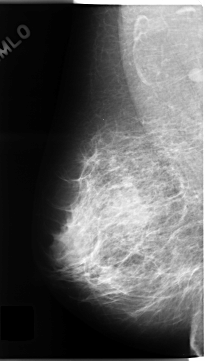

C_0136_1.RIGHT_MLO

RIGHT_MLO LINES 4688 PIXELS_PER_LINE 2656 BITS_PER_PIXEL 12 RESOLUTION 50 NON_OVERLAY